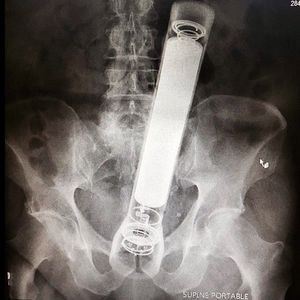

This is by far one of the weirdest foreign body I've seen in a while - a mag light! In medical terms, a foreign body or object is something that is in the body but does not belong there. Small foreign bodies are pretty common, found in the ears, nose, airways, and stomach. They can irritate, eventually causing inflammation and scarring of the tissue, not to speak about the infections they might bring. The main symptoms experienced, depending on the location of the foreign body are pain, choking, breathing problems, and nasal discharge.